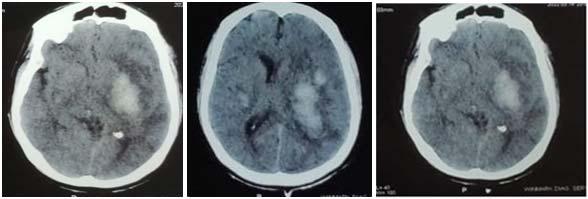

Fig 1 — CT Imaging from a patient of Basal Ganglia hemorrhage in the present study

Hemorrhage :

•Putamen hemorrhage & Basal Ganglia Hemorrhage were found to cause Swallowing dysfunction. Similar findings were reported by Maeshima S, et al37 and Logeman JA, et al respectively38

•Cerebellar Hemorrhage was found to cause Swallowing Dysfunction. Similar findings were observed by Pe’rie’ S, et al39

•Hemorrhage of PCA territory involving the Parieto-Occipital area also caused Swallow Dysfunction. Similar findings were observed by Dehaghani, et al35